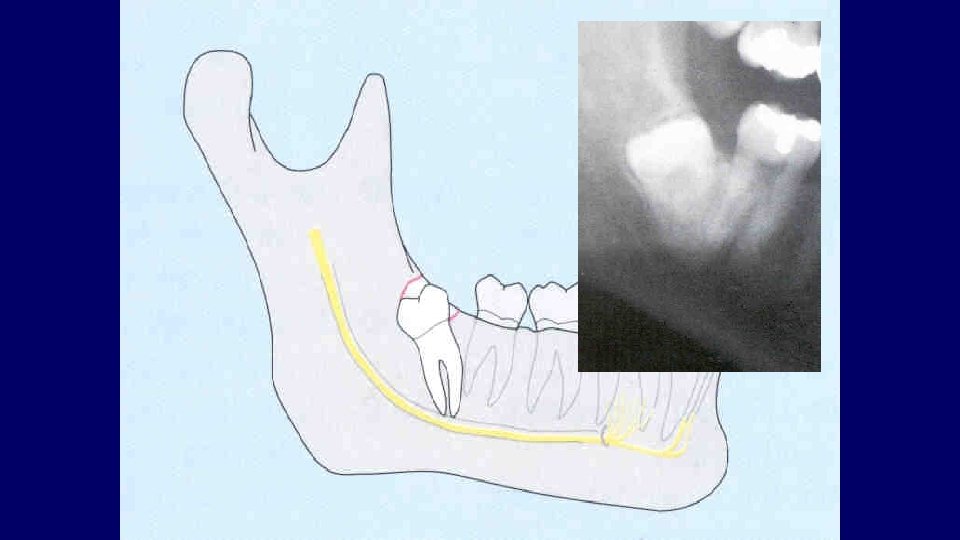

Mandibular third molar assessment (1) Type of impaction (2) Depth of impaction (3) Root pattern (4) Crown form (5) Bone density (6) Relationship to ID nerve (7) Caries (8) Position and root pattern of 2 nd molar (9) Associated pathology (10)Access

(1) Type of impaction

Types of impaction • Vertical • Mesioangular • Distoangular • Horizontal • Transverse